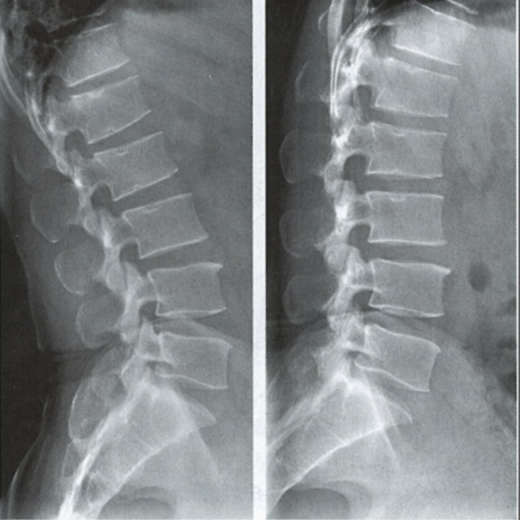

能屈能伸的腰椎——腰椎動力位

腰椎動力位,也稱為過屈過伸位,可以理解為兩個極限體位下的側(cè)位片,腰椎動力位通過做最大程度彎腰(過屈)和后仰(過伸)的動作拍攝側(cè)位片,來觀察腰椎在極限活動下的表現(xiàn)。如果說腰椎側(cè)位片能靜態(tài)體現(xiàn)椎體的解剖學(xué)結(jié)構(gòu)、序列及生理曲度改變,那么腰椎動力位則是評估腰椎動態(tài)功能性的檢查。

腰椎過伸位:是指腰部盡可能向后伸展,以雙髖關(guān)節(jié)位支撐點,運動前后骨盆位置無改變。腰椎過伸時,向前的曲度大于生理曲度,上部向后傾斜。

腰椎過屈位:是指腰部盡可能向前彎曲,以雙側(cè)髖關(guān)節(jié)位支撐點,運動前后骨盆位置無改變。腰椎過屈的表現(xiàn)位向前的曲度減小、變直,上部向前傾斜。

當(dāng)1度及以上的滑脫時才可以在普通腰椎側(cè)位上觀察到,而1度以下的滑脫或失穩(wěn)則在普通側(cè)位片上難以發(fā)現(xiàn),這時候就需要借助腰椎動力位進(jìn)行診斷。

腰椎動力位 左圖為過伸位、右圖為過屈位